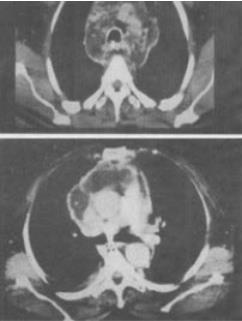

5、 患者男,64岁,患糖尿病,最近3天出现发热,伴颈静脉显露,结合CT图像,最可能的诊断是()。

- A、坏死性纵隔炎

- B、纵隔淋巴瘤

- C、侵袭性胸腺瘤

- D、恶性畸胎瘤

- E、纵隔脓肿

【正确答案-参考解析】:参加考试可见 点击进入查看